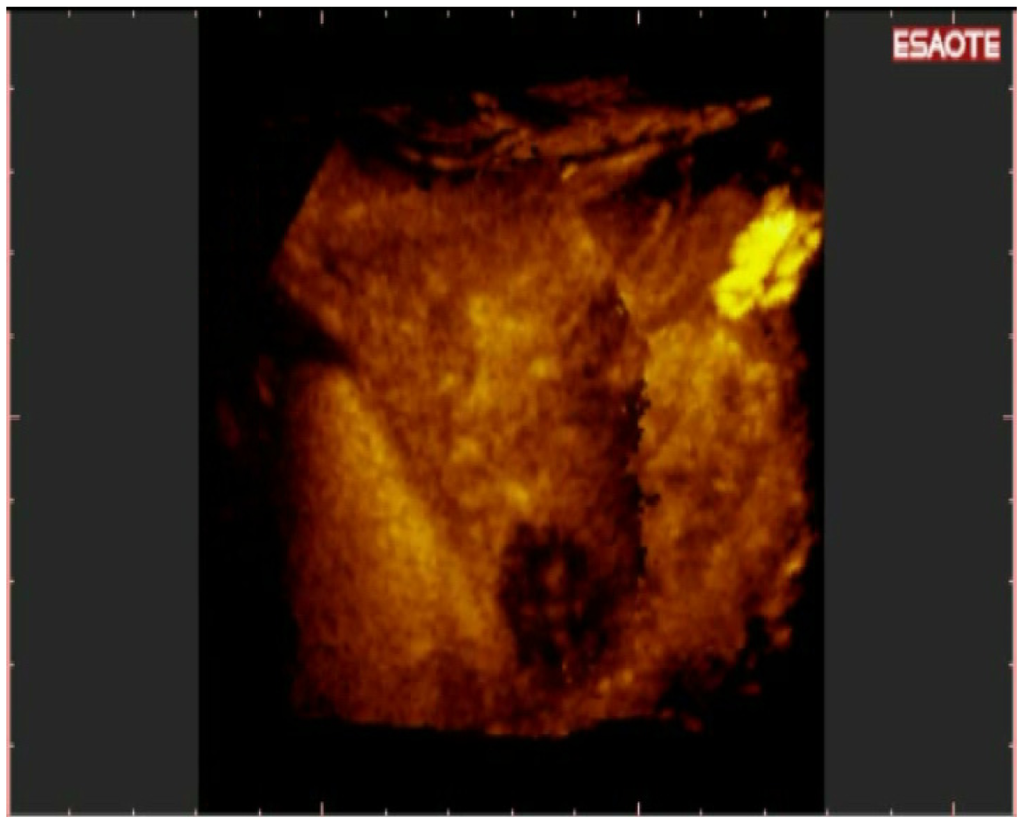

To easily perform a 3-D reconstruction of a 2-D acquisition of CEUS imaging of the whole liver, the 2-D acquisition is performed with real time scanning perpendicularly on the long-axis of the liver, for a complete 2-D image of its short-axis (Figure 2). The subsequent reconstructions of these planes show a rendered volume with a “parenchimal” aspect (Figure 5) or with a “vascular” map (Figure 6) of all the hepatic segments with an acquisition in the early arterial and in portal phase.

3-D NAV CEUS correctly detected all the local recurrences, 92/98 (93.87%) of new nodules (Figure 7) and 26/28 (92.8%) multinodular HCC (Figure 8 and Figure 9) (the same patient with small multinodular HCC false negative also for spiral CT). Dimensions of eight false negative for 3-D NAV CEUS were: Six nodules less than 2 cm, two 3 cm; their segmental distribution was: Four nodules in segment IV and four nodules in segment VI. In two cases 3-D NAV CEUS erroneously diagnosed an artero-venous malformation as new HCC (false positive) (confirmed by MRI and follow-up).